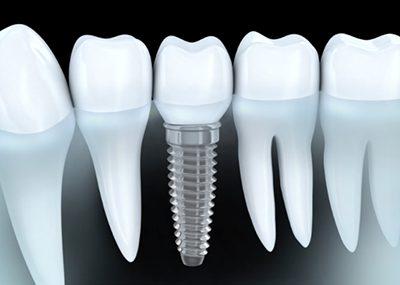

Comparable à une racine artificielle, l’implant dentaire est un petit objet cylindrique de la forme d’une vis qu’un chirurgien-dentiste fixe dans l’os maxillaire du patient. Deux a trois mois sont nécessaires à son intégration osseuse. Il remplace la racine de la dent perdue qui offre ainsi une base robuste pour accueillir une couronne, un bridge ou une prothèse dentaire amovible, et permettre au patient de mastiquer normalement et sans encombres.